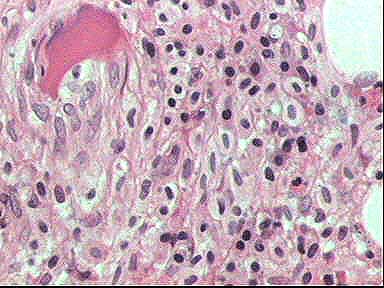

Figura 8.. H&E x400